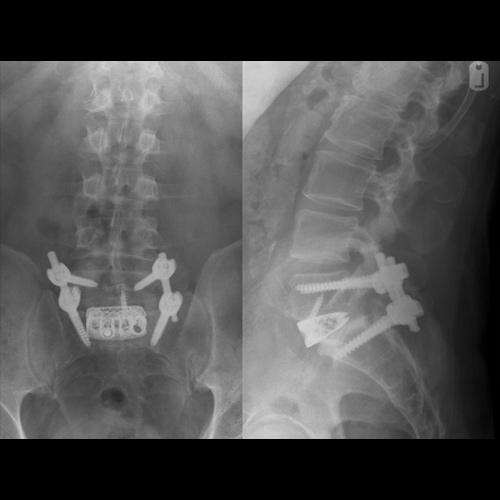

Spinal stenosis (Lumbar) Spinal stenosis (Cervical) Spinal stenosis (Thoracic) Lumbar Disc Herniation Spondylolisthesis Cervical Foraminal Stenosis Vertebroplasty Lumbar Fusion Anterior Cervical Fusion (ACDF) Posterior Cervical Fusion Thoracic Fusion Revision Lumbar Fusion Surgery Facet Joint Cyst Spinal Tumour Minimally Invasive Lumbar Fusion (XLIF) Minimally Invasive Lumbar Fusion (ALIF) Lumbar Fusion (TLIF) Thoraco-lumbar Fusion Lumbar Corpectomy Complex Lumbar Spine Surgery (Spino-pelvic fixation) Complex Cervical Spine Surgery Complex Thoracic Spine Surgery Occipito-cervical Fusion Minimally invasive surgery for thoracic disc herniation Other Related Topics